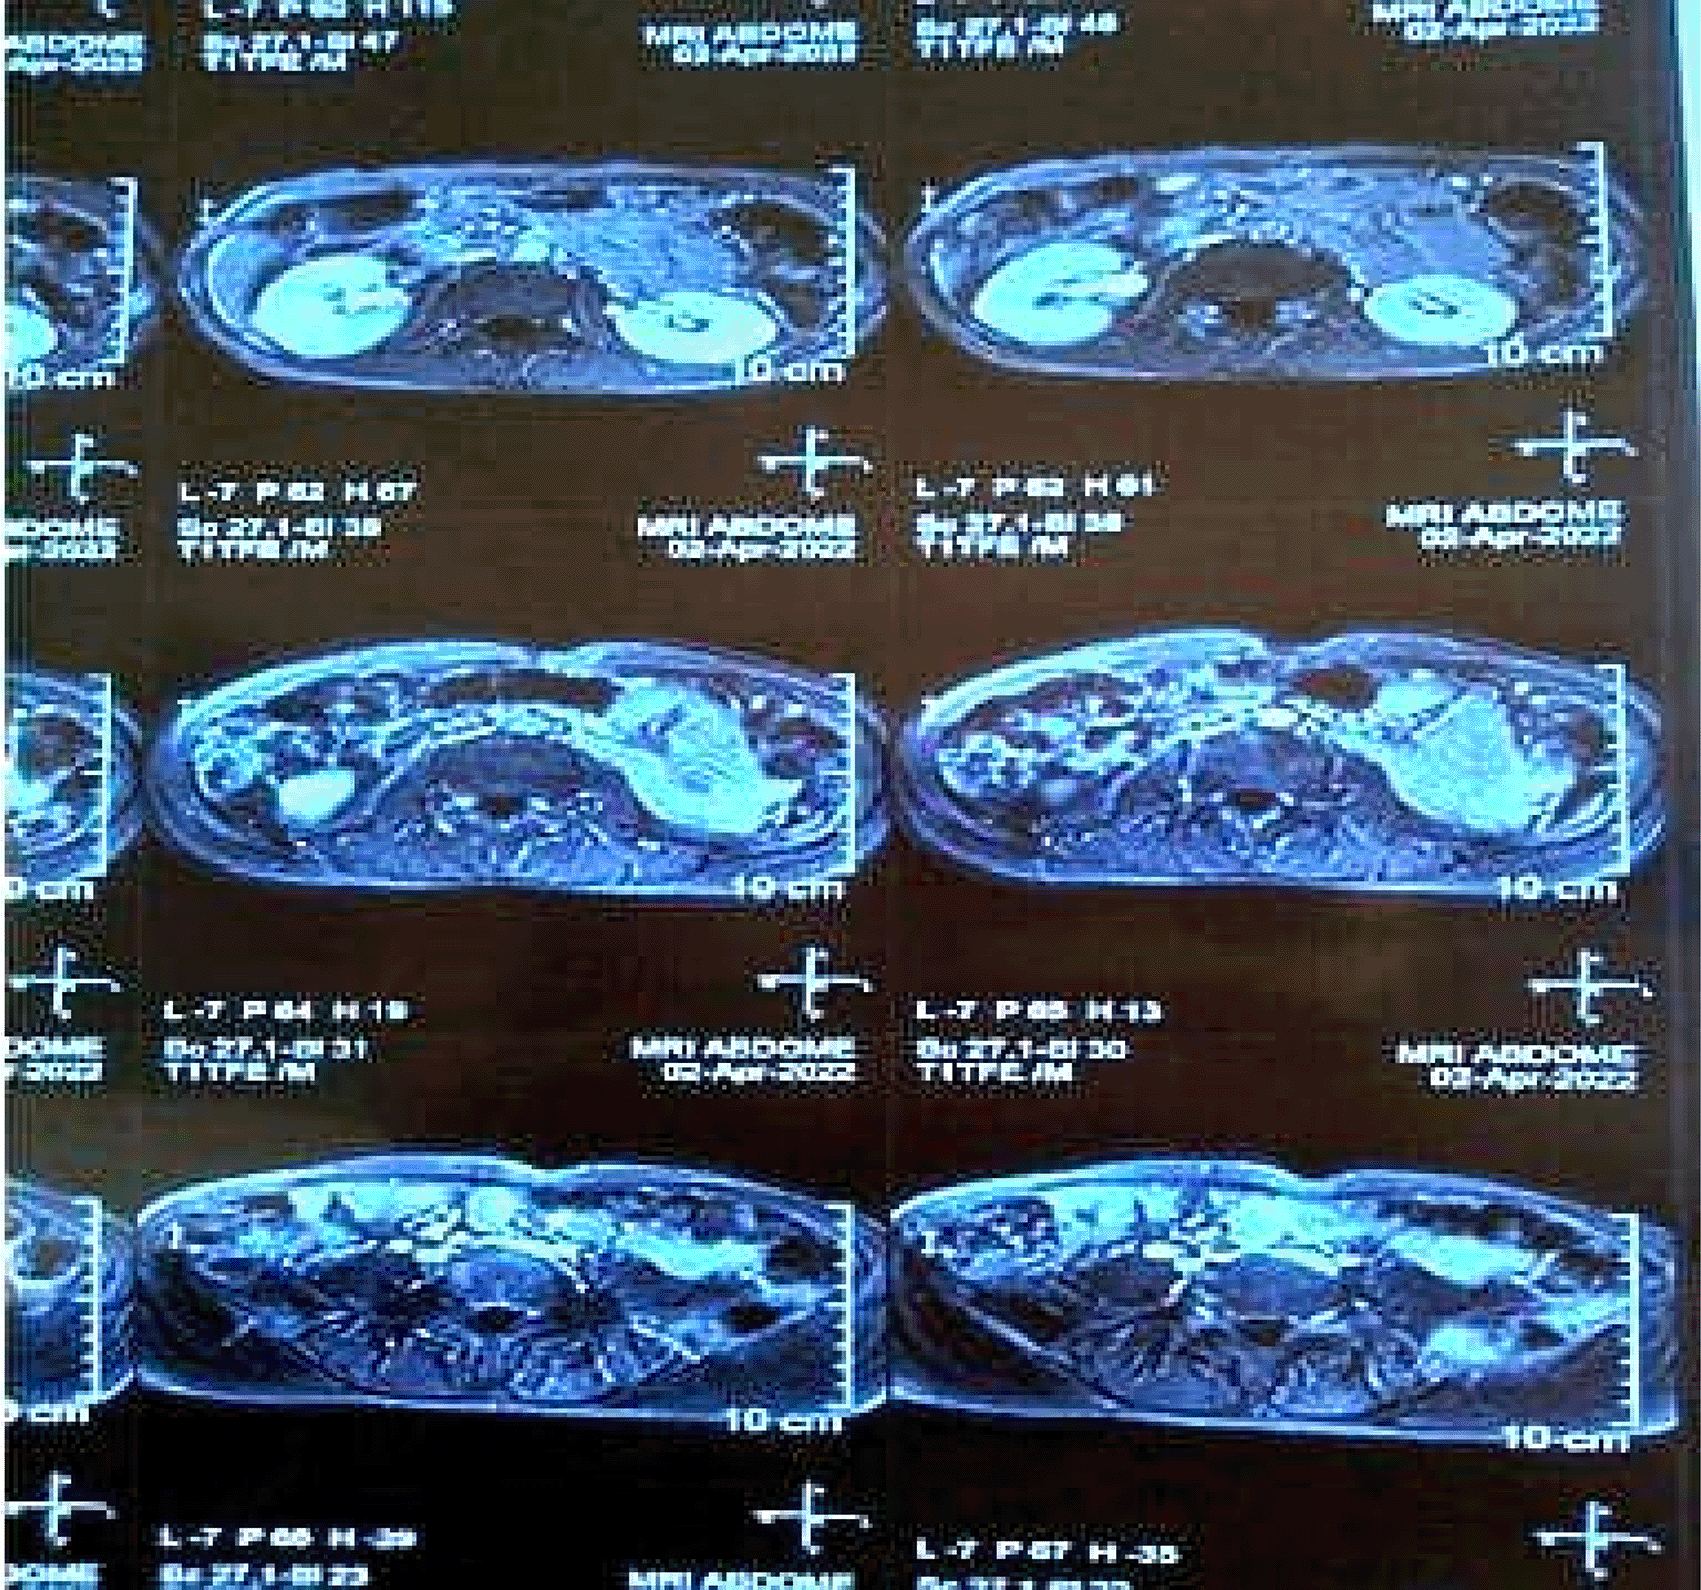

• MRI Abdomen ( Figure 6): Revealed a focal cystic lesion measuring 13x12 mm in the pancreatic tail, consistent with a pancreatic neuroendocrine tumor.

These findings underscored the multisystem involvement characteristic of MEN1, integrating features of hyperparathyroidism and neuroendocrine tumors. A detailed summary of these findings is provided in Table 1.

Advanced imaging techniques play a central role in localizing tumors and guiding management. Tc99 MIBI scans are highly effective for identifying parathyroid adenomas, as demonstrated in both cases. MRI and CT imaging further delineate the extent of organ involvement and assess for metastatic disease. In Case 2, MRI revealed osteolytic skull lesions and a pancreatic tail neoplasm, underscoring the systemic involvement of MEN1.7